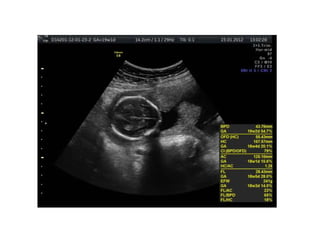

Down Syndrome:

• 48.